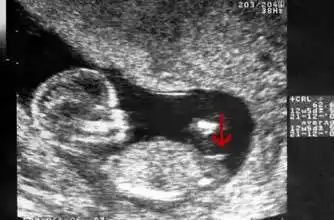

孕 周二维超声示胎儿男性外生殖器,呈「郁金香征」